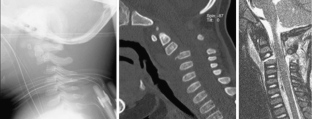

A toddler suffered a CSI without neurological deficits after a stair fall. Computer tomography (CT) and magnetic resonance imaging (MRI) of the cervical spine revealed an instable luxation fracture of C2/3. As repositioning in the halo vest immobilization failed, surgical fusion was indicated.

Via a posterior midline approach, the lamina of C2 and C3 was conflated in a modified sublaminar wiring technique using non-resorbable sutures, sparing the ossification zones of the vertebral arches. Postoperative immobilization in a halo vest facilitated bony fusion of the laminae at C2/3 without lordotic displacement of the cervical spine.